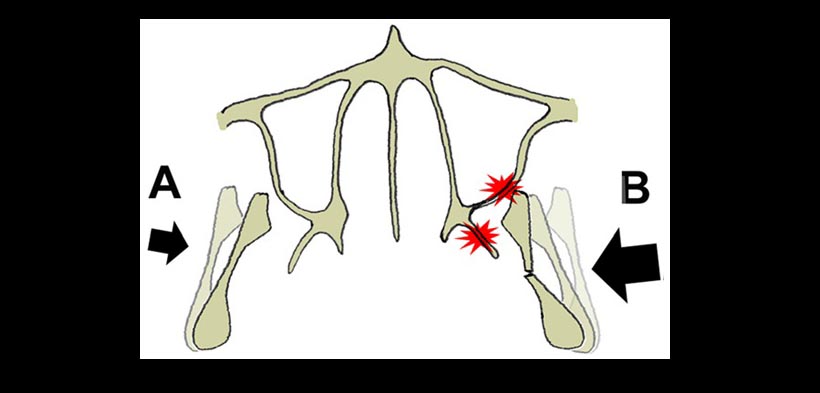

Figura 4. Modelo propuesto del probable mecanismo de acción de fracturas maxilares posteriores. Fuerza lateral se producen en la mandíbula al momento del trauma (flechas) y se produce un desplazamiento en sentido medial del proceso coronoides y puede inducir fracturas maxilares posteriores y de la apófisis pterigoides simultáneamente con subluxación transitoria o la rotación de la articulación temporomandibular.